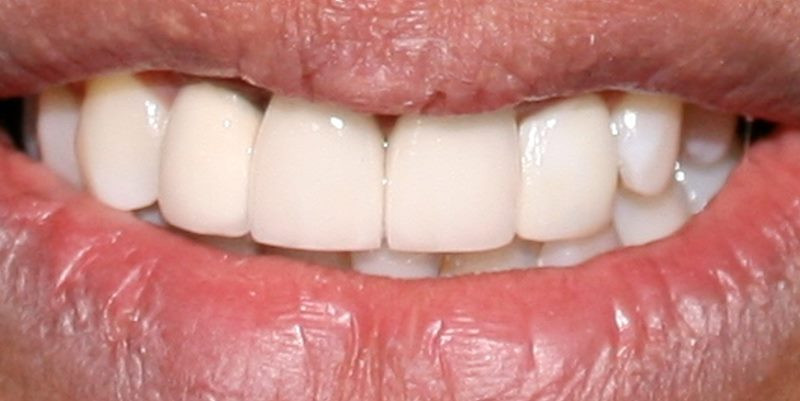

Después

Restauraiones finales colocadas en boca del paciente